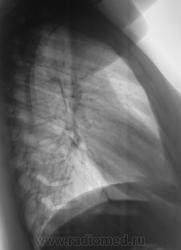

К постановке диагноза подошли формально. На 1 место поставили гамартому. на 2 - туберкулому.

Месяц тому пациентку прооперировали в ОПТД, верификация - "туберкулома".